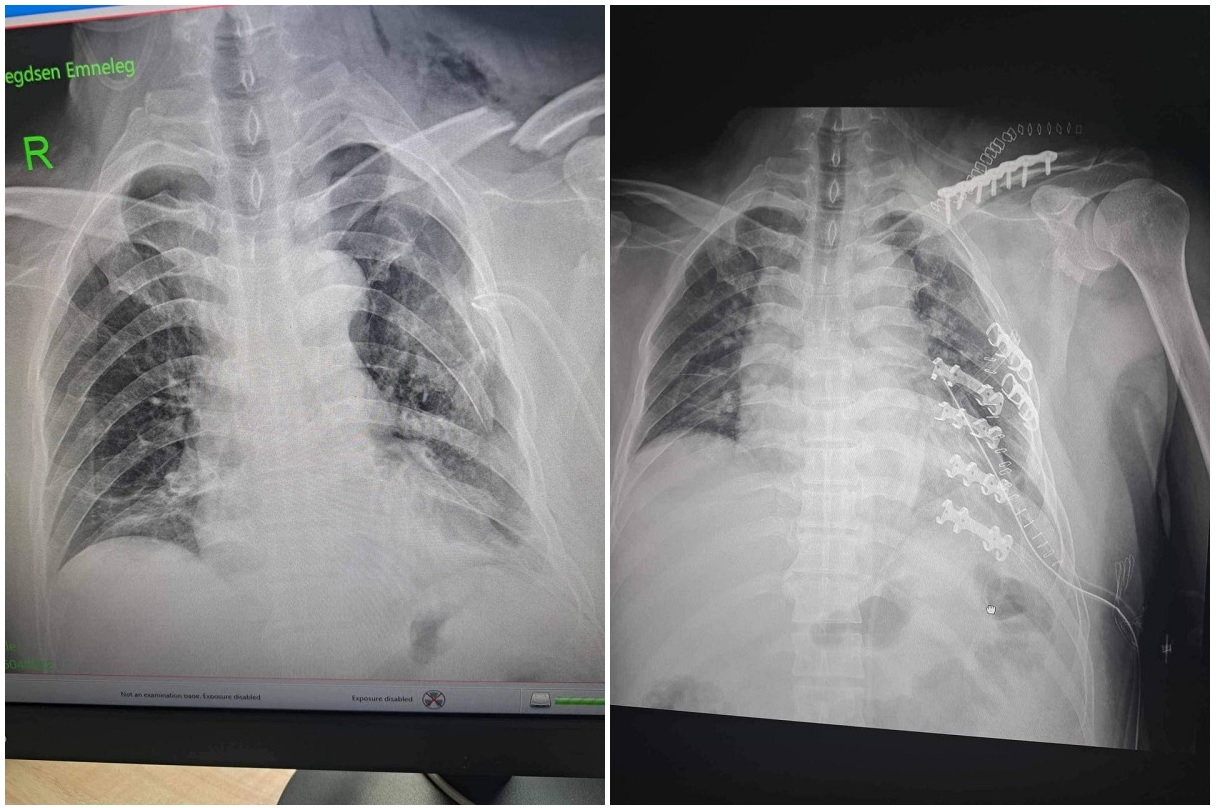

Тодруулбал, ГССҮТ-ийн мэс заслын баг бүрэлдэхүүн аймгийн нэгдсэн эмнэлгийн гэмтлийн эмч Д.Наранбаатар, мэдээгүйжүүлгийн эмч Э.Алтанхуяг, мэдээгүйжүүлгийн сувилагч П.Дуламцэцэг, мэс заслын сувилагч А.Цэрэндолгор, Д.Дэлгэрмаа, асрагч И.Болор-Эрдэнэ нартай хамтран тухайн өвчтөний олон хавирганы тогтворгүй хугарлыг бэхлэх мэс заслыг амжилттай хийсэн байна.

Өвчтөний биеийн байдал сайжирч, тогтвортой байгаа бөгөөд өдгөө аймгийн нэгдсэн эмнэлэгт мэс заслын дараах эмийн эмчилгээ хийлгэж байгаа аж.